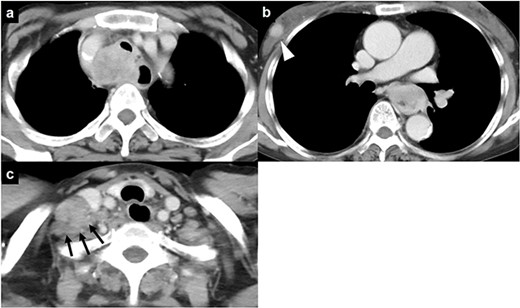

A 59-year-old woman presented in respiratory distress. We identified a mass invading the trachea in the upper mediastinum, an esophageal mass, a mass in the subcutaneous tissue of the right chest wall and a mass in the right cervical area by computed tomography (Fig. 1a–c). Fine-needle aspiration for the right cervical mass was performed, and a diagnosis of squamous cell carcinoma was obtained. The patient was diagnosed as having clinical stage IV esophageal cancer. Because of respiratory distress due to airway stenosis, we planned to place a silicon Y-stent (Dumon Y; outer diameter of the main part, 14 mm; outer diameter of the branching part, 10 mm; Novatech SA, La Ciotat Cedex, France) by rigid bronchoscopy prior to chemotherapy. Rigid bronchoscopy was performed under general anesthesia combined with extracorporeal membrane oxygenation and revealed stenosis of the trachea (Fig. 2a). When the tumor was cored out by rigid bronchoscopy, perforation of the lower trachea occurred (Fig. 2b and c). A silicon Y-stent was then inserted to cover the tracheal fistula (Fig. 2d). Chest X-ray revealed right pneumothorax, and chest drainage was performed (Fig. 3a and b). The patient was weaned from extracorporeal membrane oxygenation when spontaneous ventilation was maintained; this was done in the operating room.

Chest computed tomography of a 59-year-old woman who was admitted to our hospital; (a) a mass is visible invading the trachea in the upper mediastinum; (b) an esophageal mass and a mass in the subcutaneous tissue of the right chest wall (arrowhead) are visible; (c) a mass in the right cervical region is also present (black arrows).